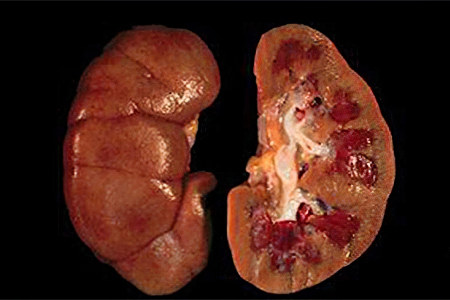

• Заболевания почек. Уничтожение клеток почек ухудшает их функционирование. Это может происходить при гломерулонефрите, волчаночной нефропатии, пиелонефрите, отторжении пересаженного органа, тромбозе почечных вен и пионефрозе.

• Онкологические заболевания почек. Разрастающаяся опухоль разрушает почечные ткани, что приводит к нарушениям в их работе.